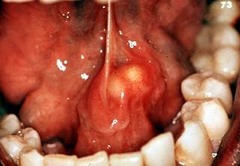

benign tumor of epithelium; pedunculated; cauliflower like appearance; found mostly on palatal area/uvula

Front

Papilloma